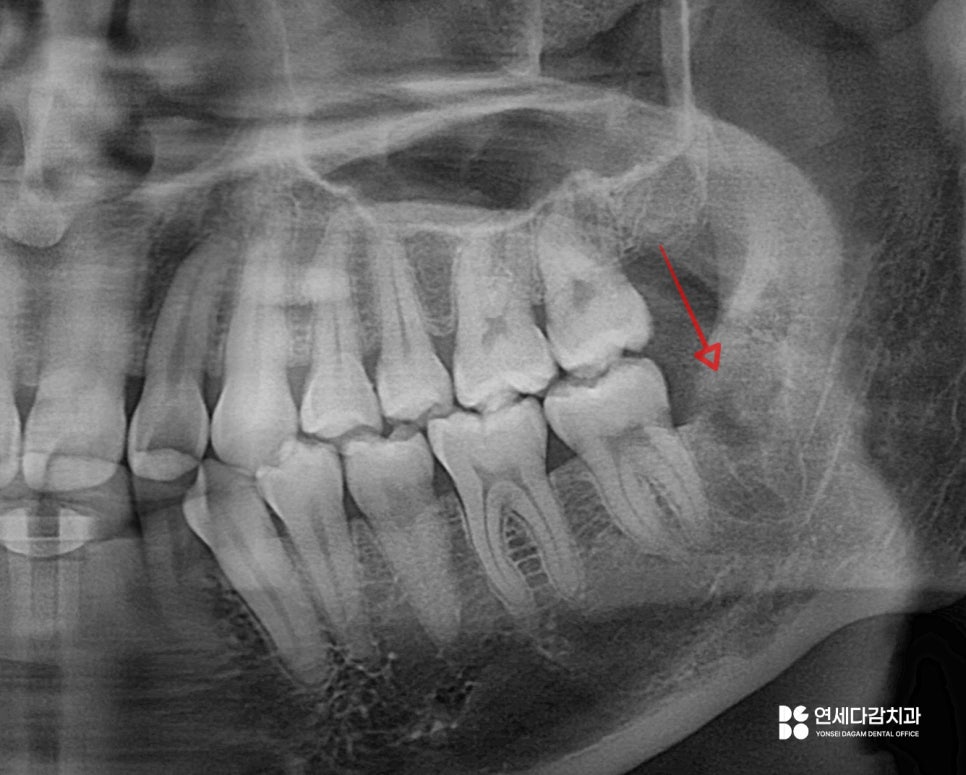

앞쪽(근심)부분은 밖으로 나왔지만,

뒤쪽(원심)은 잇몸 속에 묻혀 있습니다.

이를 오금역 치과 에서 평가했을 때

후방으로 경사진 형태로 짐작됩니다.

지금처럼 치관이 제대로 나오지 못한 경우

앞어금니와의 사이에 공간이 형성되어

음식물과 세균은 쉽게 들어갑니다.

반면 칫솔질이 제대로 되지 않는

청결의 사각지대가 만들어집니다.